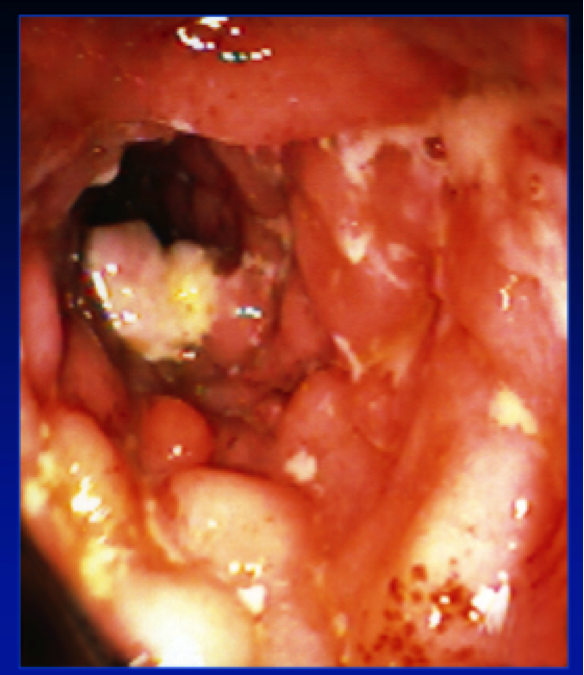

What disease? features?

Crohn’s.

characteristic endoscopic features of nodularity, ulceration, exudate and luminal narrowing